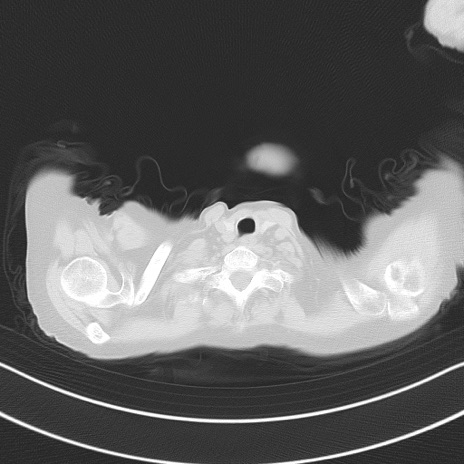

他院CT

冠状断像

矢状断像